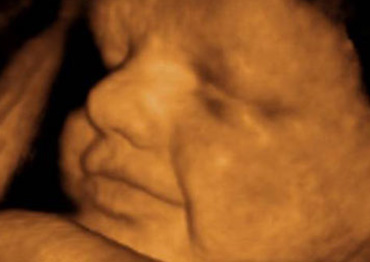

Tecnología avanzada para monitorear el desarrollo fetal, proporcionando información precisa y oportuna.

Evaluación continua y precisa del estado fetal, mediante tecnología de ultrasonido avanzada, para asegurar un desarrollo óptimo y detectar posibles complicaciones de manera temprana.